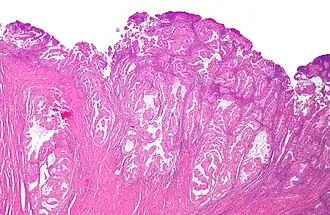

Histologisch preparaat van endometriaal adenocarcinoom, de meest voorkomende vorm van baarmoederkanker, gekleurd met hematoxyline en eosine.

Baarmoederkanker[1] of endometriumcarcinoom[1] is een vorm van kanker gelokaliseerd in het lichaam van de baarmoeder. Anders dan baarmoederhalskanker zijn nagenoeg alle gevallen van baarmoederkanker van het adenocarcinoom type. In 2005 werd in Nederland bij ongeveer 1850 vrouwen de diagnose baarmoederkanker gesteld. Het is de meest voorkomende vorm van kanker van de vrouwelijke geslachtsorganen. In hetzelfde jaar stierven in Nederland ruim 400 vrouwen aan de gevolgen van deze kanker. De vijfjaarsoverleving is 80% en is vergelijking met andere vormen van kanker relatief gunstig.[2]